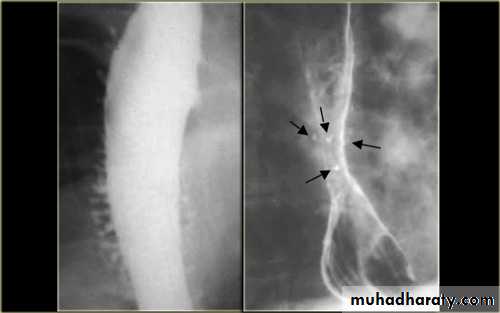

Stricture

Benign vs. malignant Causes Specific locationContrast study EUS CT